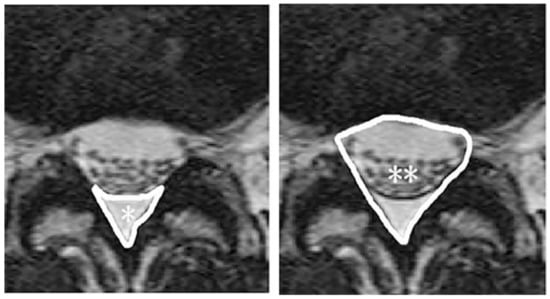

- Ishihara, S.; Fujita, N.; Azuma, K.; Michikawa, T.; Yagi, M.; Tsuji, T.; Takayama, M.; Matsumoto, H.; Nakamura, M.; Matsumoto, M.; et al. Spinal epidural lipomatosis is a previously unrecognized manifestation of metabolic syndrome. Spine J. 2019, 19, 493–500. [Google Scholar] [CrossRef] [PubMed]

- Spinnato, P.; Ponti, F.; de Pasqua, S. MRI diagnosis of obesity-related spinal epidural lipomatosis. Can. J. Neurol. Sci. 2020, 47, 124–125. [Google Scholar] [CrossRef] [PubMed]